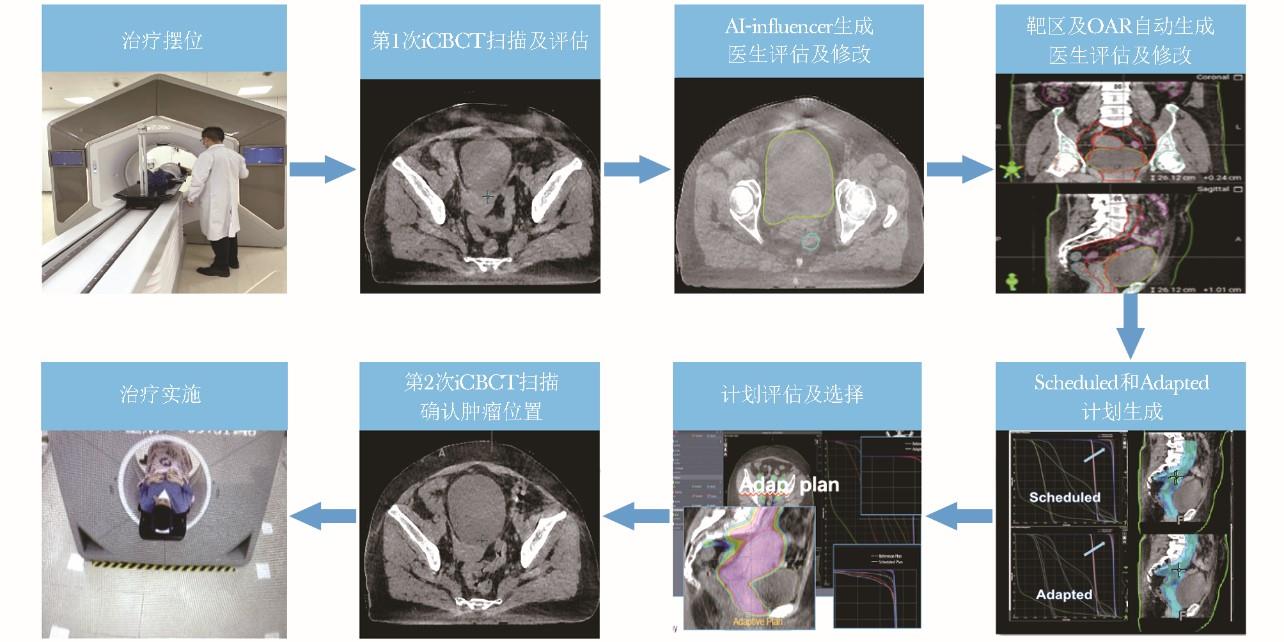

它是通过每次治疗前的高清图像引导技术(IGRT),评估患者的器官解剖和生理变化,或治疗过程中的反馈信息如肿瘤的解剖位置及大小,分析分次放疗与初始放疗计划设计间的差异,根据当下的变化对治疗方案每次实时做出调整。

在线自适应放疗在这方面具有很多明显的优势。在线自适应放疗可解决治疗过程中肿瘤位置和形状变化问题,特别适合每个分次间肿瘤自身或受周围正常器官位移影响变化大的病例;且与离线自适应相比,患者在放疗分次内无需离开治疗床,对治疗前扫描图像能重新快速制定治疗方案并实施,从而能够实现每次肿瘤精准放疗,既提高靶区照射准度,同时更好地保护肿瘤周围的正常组织。

在线自适应放疗整体治疗流程